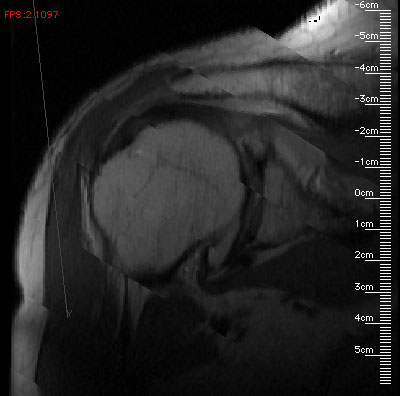

The program presents the user with two windows-- the smaller window has zoom and translation controls, and the larger window serves as both the output window and allows the user to easily and interactively rotate the block of data. I use an interactive rotation input system similar to the Volrend system's [Standish, 1995] virtual trackball. An actual screen image from the program is below.

The images have rulers which display millimeter distances, matched to the zoom factor. If the user drags the mouse inside the image window (labeled "Slice 3D") the block of data rotates beneath the mouse. If the user clicks the mouse in the image window, the program computes the 3D coordinates (in millimeters) of the clicked point on the slicing plane, and writes them to standard output. These coordinates could then be captured to a file and passed to another program for further analysis (e.g., for MRI geometric calibration, estimating the volume of a lesion, or planning a minimally harmful path for radiation treatment).